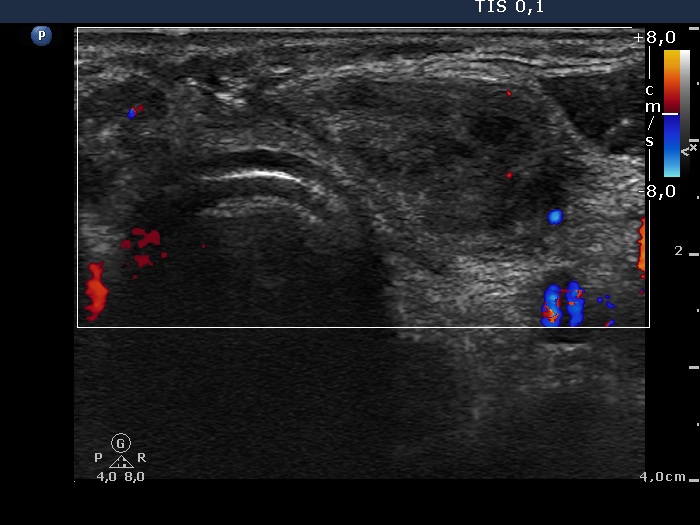

Six years after surgery (first row of images):

Clinical data: A 61-year-old man underwent bilateral thyroid surgery six years ago. According to the final report, total thyroidectomy was performed. Histopathology disclosed benign hyperplastic nodules. Several months before the present examination, the patient noticed a painless mass in the left lobe.

Palpation: a hard, painless mass according to the left lobe.

Laboratory tests: TSH 1.05 mIU/L on daily 87.5 microgram levothyroxine.

Ultrasonography. Muscle fiber and connective tissue was found in the right thyroid bed. Hypoechoic mass was found according to the palpable mass in the left lobe. It had a more hypoechoic discrete lesion with echogenic figures. The mass was avascular.

Cytology resulted in granulation around surgical thread.

A surgical consultation was proposed.